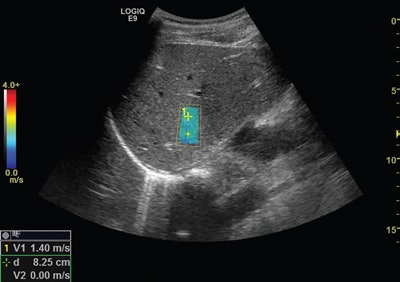

This latest offering includes Logiq E9 XDclear 2.0, a new processing chain that optimizes the imaging process from the pulse of the probe to each of its pixels, delivering excellent image quality across a wide variety of cases, according to GE. The availability of extra tools such as 3D GPS Markers, MRI Auto-Registration and specialty probes will enhance its value, the company says.